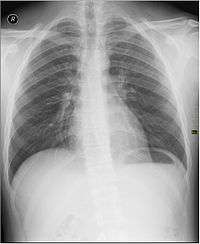

A radiograph of a person's chest

Interventional radiology (IR or sometimes VIR for vascular and interventional radiology) is a subspecialty of radiology in which minimally invasive procedures are performed using image guidance. Some of these procedures are done for purely diagnostic purposes (e.g., angiogram), while others are done for treatment purposes (e.g., angioplasty).

The basic concept behind interventional radiology is to diagnose or treat pathologies, with the most minimally invasive technique possible. Minimally invasive procedures are currently performed more than ever before. These procedures are often performed with the patient fully awake, with little or no sedation required. Interventional Radiologists and Interventional Radiographers[5] diagnose and treat several disorders, including peripheral vascular disease, renal artery stenosis, inferior vena cava filter placement, gastrostomy tube placements, biliary stents and hepatic interventions. Images are used for guidance, and the primary instruments used during the procedure are needles and catheters. The images provide maps that allow the Clinician to guide these instruments through the body to the areas containing disease. By minimizing the physical trauma to the patient, peripheral interventions can reduce infection rates and recovery times, as well as hospital stays. To be a trained interventionalist in the United States, an individual completes a five-year residency in radiology and a one- or two-year fellowship in IR.[6]